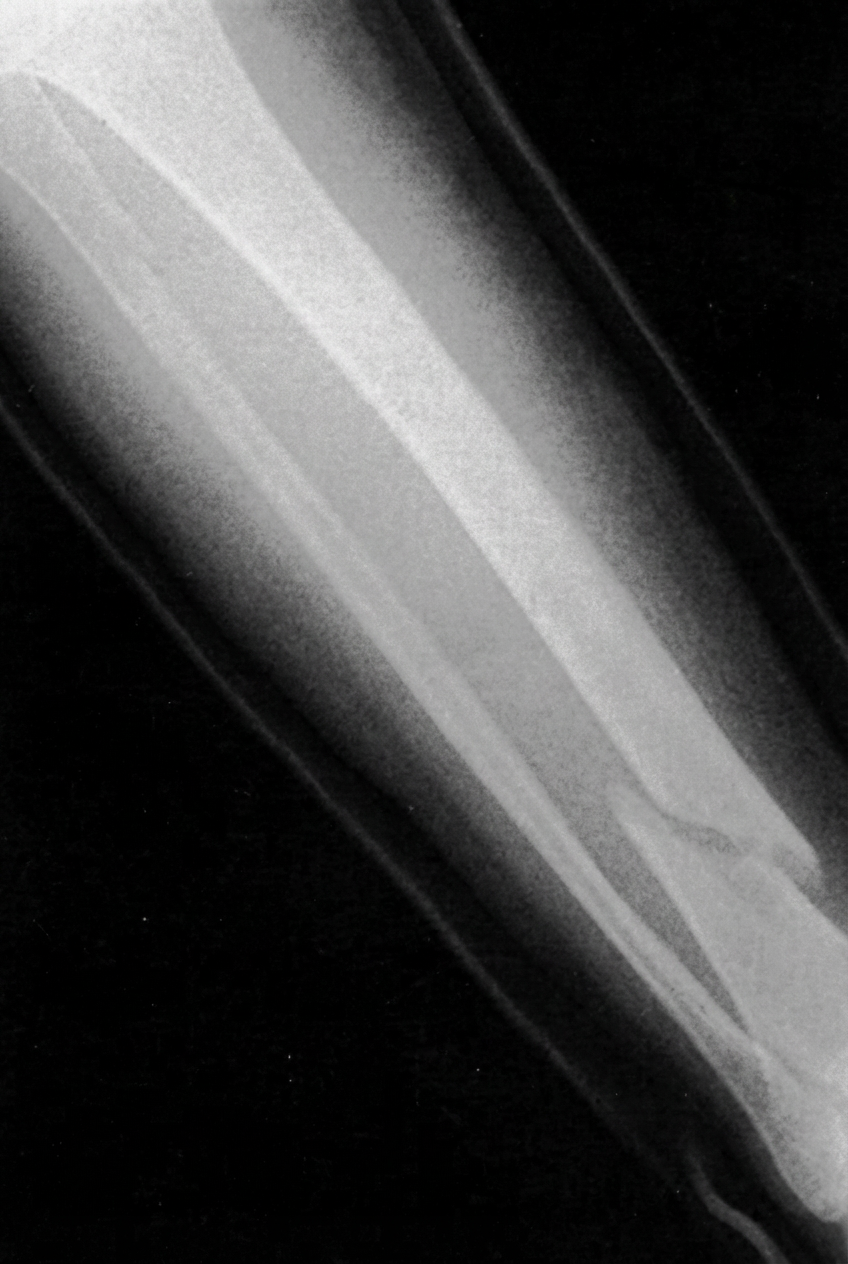

Radiographie d’un os de jambe humaine brisé, situation désastreuse sans notre système intégré de réparation. Cette capacité étonnante de maintenance de notre squelette montre la main d’un créateur bienveillant. Image: Tsu Nimh, www.sxc.hu

Réparation:

Bien que le squelette humain soit capable de beaucoup de choses, il arrive que les contraintes qu’on lui impose soient un peu trop fortes. Les week-ends de ski se terminant avec une jambe cassée sont bien connus ! Heureusement notre squelette possède un système de réparation intégré, qui opère en deux phases. La première dépose les fibres osseuses en suivant un tissage aléatoire. C’est rapide mais relativement peu solide. Cependant, elle est suivie d’une deuxième phase où les fibres se déposent plus lentement mais suivant une disposition lamellaire plus solide. Ainsi le corps opère un « rafistolage » rapide suivi d’une réparation en profondeur plus longue. Une fois encore on doit se demander comment cela aurait pu se développer graduellement par évolution ? Il y a là toutes les marques d’une stratégie mûrement préparée. Cela ressemble plutôt aux services d’un secouriste suivis d’un traitement hospitalier élaboré : c’est un plan complet de service de santé.